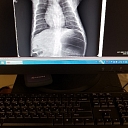

Pļavnieki, veterinary clinic, LTD Anivet

Animal treatment